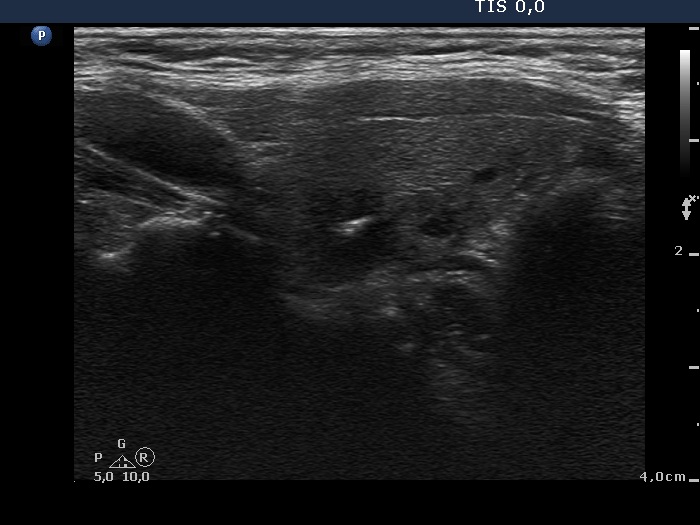

Ultrasonography. The thyroid was echonormal. There were multiple moderately hypoechogenic nodules in the right lobe making the appearance micronodular. There was a relatively larger hyperechogenic nodule in the isthmus. The left lobe contained a hypoechogenic lesion, which presented blurred borders, microcalcifications and an increase intranodular blood flow.